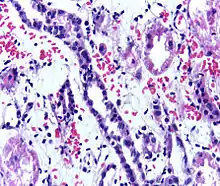

Acute rejection is another possible complication of kidney transplantation; it is graded according to the Banff Classification which incorporates various serologic, molecular and histologic markers to determine the severity of the rejection. Acute rejection can be classified as T-cell mediated, antibody mediated or both (mixed rejection). Common causes of acute rejection include inadequate immunosuppression treatment or non-compliance with the immunosuppressive regiment.[72] Clinical acute rejection (seen in approximately 10-15% of kidney transplants within the first year of transplantation) presents as kidney rejection with associated kidney dysfunction.[72] Subclinical rejection (seen in approximately 5-15% of kidney transplants within the first year of transplantation) presents as rejection incidentally seen on biopsy but with normal kidney function.[72] Acute rejection with onset 3 months or later after transplantation is associated with a worse prognosis.[72] Acute rejection with onset less than 1 year after transplantation is usually T cell mediated, whereas onset greater than 1 year after transplantation is associated with a mixed T cell and antibody mediated inflammation.[72]